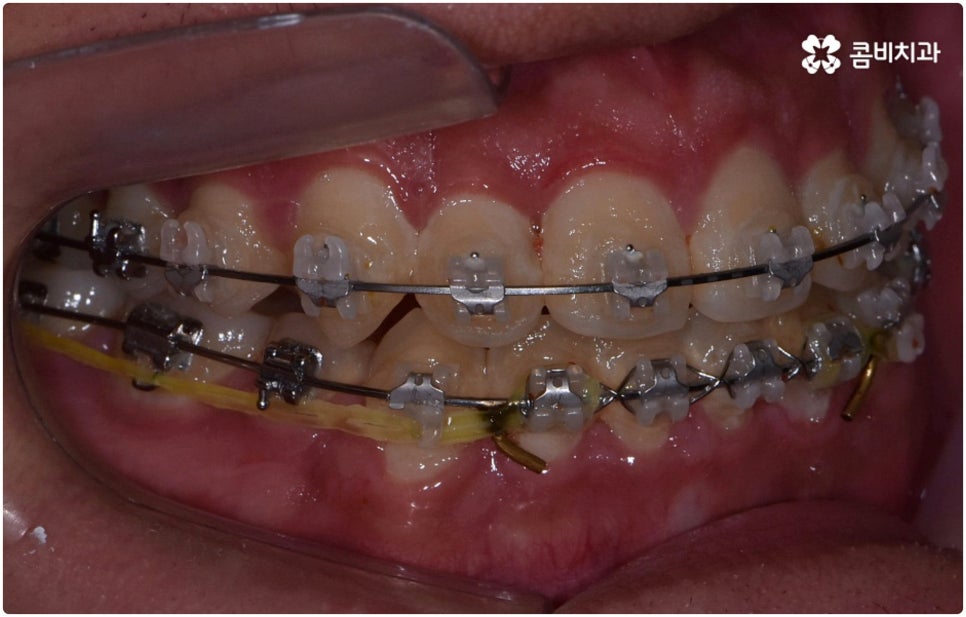

부정교합은 부정교합 1급, 부정교합 2급, 부정교합 3급 이렇게 세가지 종류로 나눌 수 있는데요. 부정교합 1급은 이를 다물었을 때 위아래 어금니는 잘 맞물리지만 덧니가 있거나 치아 사이가 살짝 벌어져 있는 경우처럼 치열이 삐뚤어진 경우를 말하는 것으로 골격이나 구조적인 부분에는 크게 문제가 없기 때문에 정도가 심하지 않다면 보다 빠르고 간편한 교정 치료가 가능한 케이스라고 할 수 있어요. 부정교합 2급은 상악이 하악보다 더 튀어나온 상태로 위에서 언급했던 무턱, 돌출입이 여기에 속하며 반대로 부정교합 3급 은 주걱턱처럼 하악이 상악보다 튀어나온 상태를 의미하고 있습니다.

환자분들마다 상황은 모두 다르기 때문에 부정교합 교정 치료를 할 때는 정밀 검진 후 맞춤 치료 계획에 따라 무리하지 않게 진행하는 것이 중요한 포인트라고 할 수 있어요. 이때 구강내 상태 (치아, 잇몸, 치열, 교합 등) 뿐 아니라 구강 외 상태 (뼈의 위치 및 구조 발달, 얼굴 정면과 측면 등 안모 비율) 와 같은 모든 부분을 꼼꼼하게 촬영하고 환자의 연령 및 생활 습관 등을 종합적으로 고려하여 원인을 분석한 다음 치아를 어떻게 얼마나 움직여야할지 면밀하게 교정 플랜을 세우는 것이 필요하므로 3D CT, 모르페우스 같은 정밀 진단 기계를 갖추고 있는 치과에서 다양한 임상 경험을 통해 뛰어난 기술력을 가지고 있는 담당의 선생님께 치료 받으시길 권유드리고 있습니다.

부정교합 2급, 부정교합 3급 과 같이 구조적인 부분에 원인이 있는 문제라면 잇몸뼈가 다 굳고 난 다음인 중장년 성인분들의 경우 교정 치료를 받는 것이 과연 부정교합 개선에 효과가 있을까 궁금해 하실 수 있어요. 특히 턱관절 이상 문제는 수술을 통해서만 고칠 수 있다고 알고 계셨던 분들은 부담을 느끼고 치료를 미루셨을 수 있는데요. 물론 성인분들의 경우 상황에 따라, 예를 들어 정도가 매우 심한 부정교합 3급 케이스라면 악교정수술을 받아야 할 수도 있습니다. 또한 대부분의 부정교합 2급, 부정교합 3급 케이스들 같은 경우 초등학교 고학년에서 중학교 저학년 사이에 교정 치료를 시작하는 것이 좋다고 권유하는 것도 사실인데요, 그 이유는 아무래도 치아 이동 속도가 빠르고 전반적인 발달 상황에 맞추어 자연스럽게 치료를 진행할 수 있는 성장기의 특성상 이 시기부터 지속적으로 턱뼈 크기 부조화를 조절하고 상하악의 올바른 성장을 유도하는 게 보다 효율적이기 때문이라고 할 수 있어요.

하지만 관련 기술 발달로 교정에 있어서 적기라는 것이 크게 의미가 없어진 근래에는 정도가 많이 심각하지 않다면 중장년 성인분들의 경우에도 각자에게 맞는 교정 치료를 통해서 얼마든지 부정교합 개선이 가능하니 안될 것이라고 지레 짐작을 하여 내원을 망설이시기 보다는 먼저 교정 치료를 위한 검진을 받아보고 자신의 상황에 대해서 숙련된 의료진과 충분히 상담해 보시길 권유드리고 있습니다. 특히 수술적인 치료를 할 때도 교합을 바로잡기 위해서는 치과와 협진하여 진행하는 케이스가 많으니 교정을 통한 부정교합 개선 및 턱관절 치료 효과에 대해 크게 의구심을 가지실 필요는 없을 거예요. 상황에 따라 교정 치료만으로도 기능적 개선은 물론 균형잡힌 안모와 호감가는 인상으로의 변화가 가능한 경우가 많으니 불편함을 참고 계시지 말고 정밀 진단과 상담부터 차근차근 시작해 보시면 필요한 도움을 받아 보실 수 있어요.